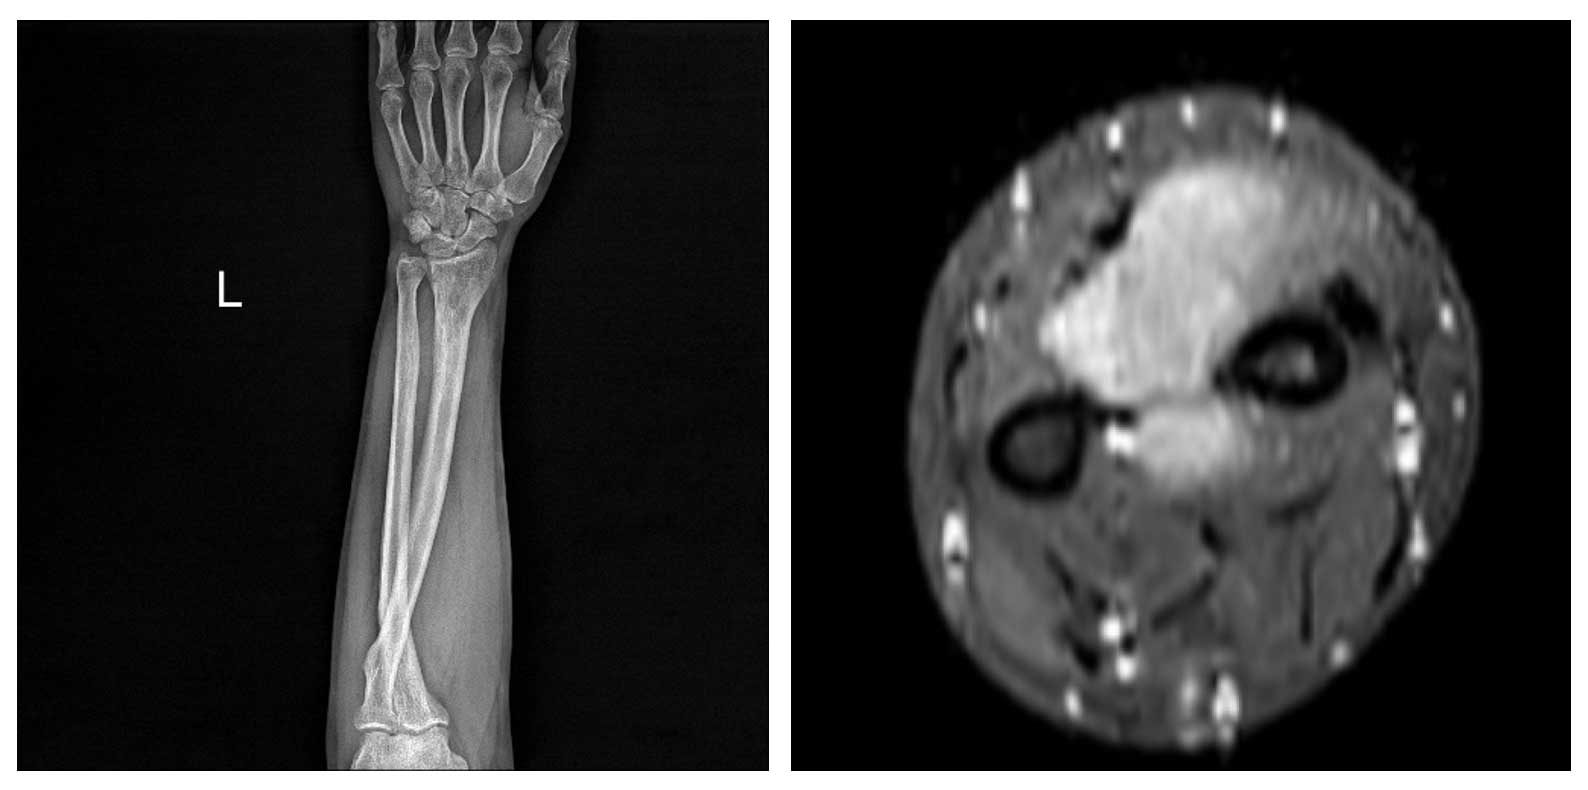

Görsel Açıklamaları

Ameliyat Öncesi: Röntgende radius distalde düzensizlik ve skleroz, MR’da çevreleyen yumuşak doku komponenti görülmekte.

Ameliyat Sonrası: Röntgende geri kazanılan kemiğin proksimal ve distalde plak ile fiksasyonu görülmekte.